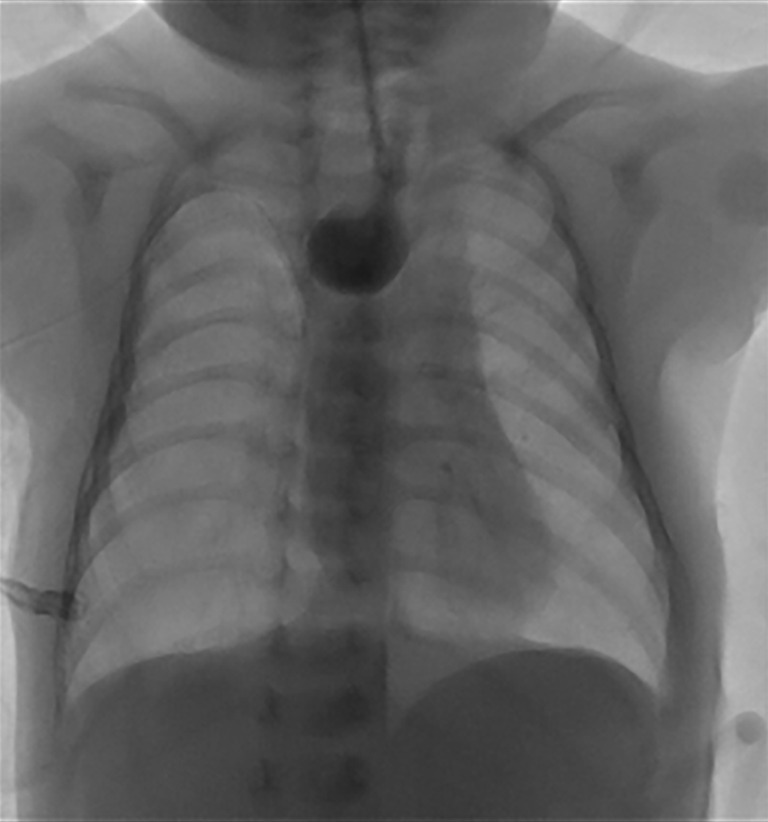

Background: Anastomotic strictures (AS) following surgical repair of esophageal atresia (EA) are the most common cause of pediatric esophageal strictures. In this retrospective cohort study, we evaluated the safety and efficacy of balloon dilation in the treatment of AS following EA repair.

Methods: Balloon dilation was performed on 31 children with AS following EA repair (the diameter of the balloon ranged from 6-15 mm). Esophagography was conducted before and after each dilation. Change from liquid diets to solid food, alleviation of vomiting, and significant weight gain during the 3 to 6 months of follow-up after balloon dilation constituted an effective treatment. The Chi-squared test was used for data analysis in this retrospective cohort study.

Results: A total of 86 balloon dilations were performed on 31 children, with 78 being successful, resulting in a success rate of 90.7%. In addition, 13 children underwent balloon dilations assisted by digital subtraction angiography (DSA). Four children developed restenosis, and one child suffered from esophageal perforation after the initial dilation. At the 3- to 6-month follow-up, the treatment was efficacious in 26 children, with an overall effectiveness rate of 84%.

Conclusions: Balloon dilation is a safe and efficacious treatment option for the treatment of AS following surgical repair of EA.